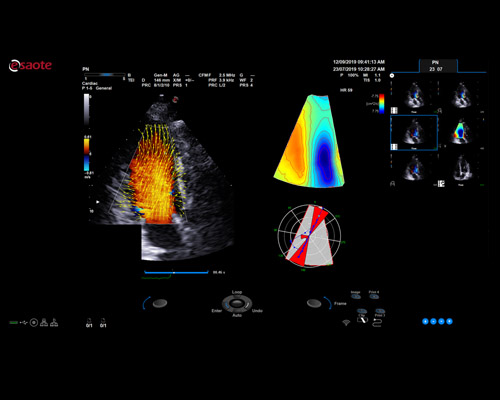

Research and successfully implement the limitless ultrasound technologies such as MicroE – Detect microcalcification; Xstrain4D – Cardiac strain 4D; XSTIC – Spatial-Temporal Image Correlation

MyLab X8 eXP integrates latest technologies, delivering high level of image quality with optimal workflow, efficiency